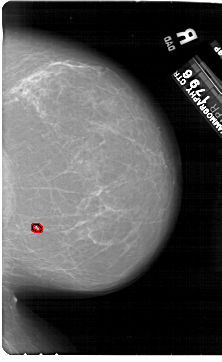

A_1923_1.RIGHT_MLO

RIGHT_MLO LINES 6526 PIXELS_PER_LINE 3976 BITS_PER_PIXEL 12 RESOLUTION 43.5 OVERLAY

FILE: A_1923_1.RIGHT_MLO.OVERLAY

TOTAL_ABNORMALITIES 1

ABNORMALITY 1

LESION_TYPE CALCIFICATION TYPE PLEOMORPHIC DISTRIBUTION CLUSTERED

ASSESSMENT 4

SUBTLETY 2

PATHOLOGY BENIGN

TOTAL_OUTLINES 1

BOUNDARY